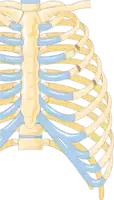

Illustration showing rib fracture at 3rd, 4th and 5th rib. -